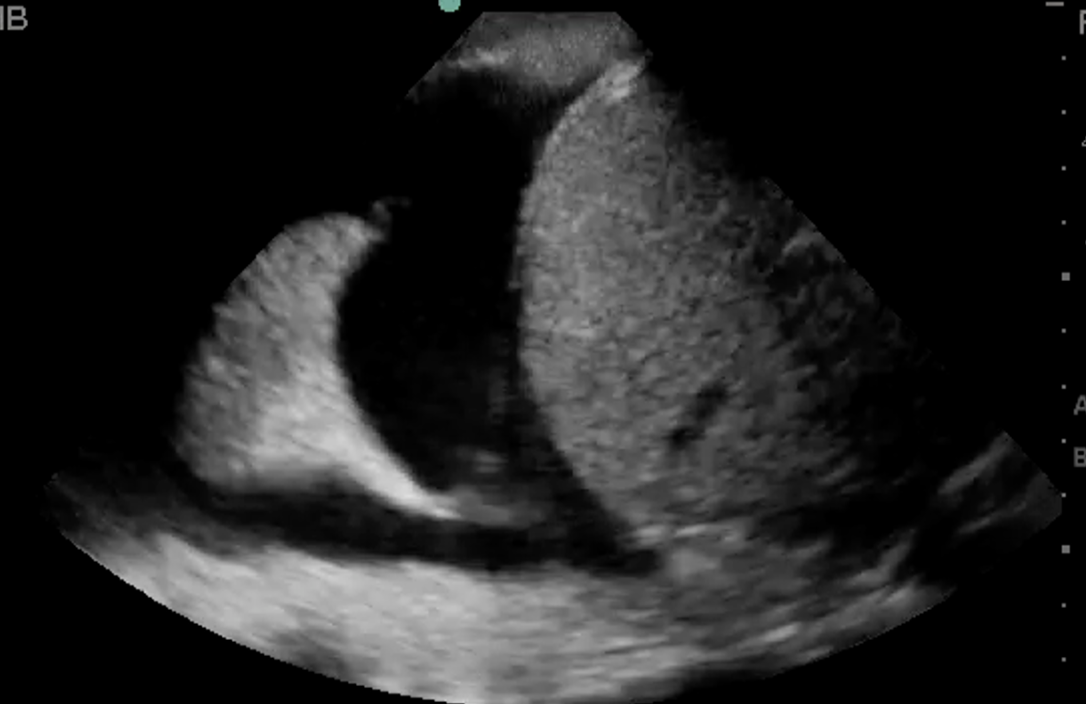

What artifact is illustrated here? (Hint: structure in thorax noted beyond the diaphgram)

Posterior acoustic enhancement – certain media allow efficient propagation of the ultrasound waves, increasing the transmission of the ultrasound wave; the tissue behind the media appears more echogenic.